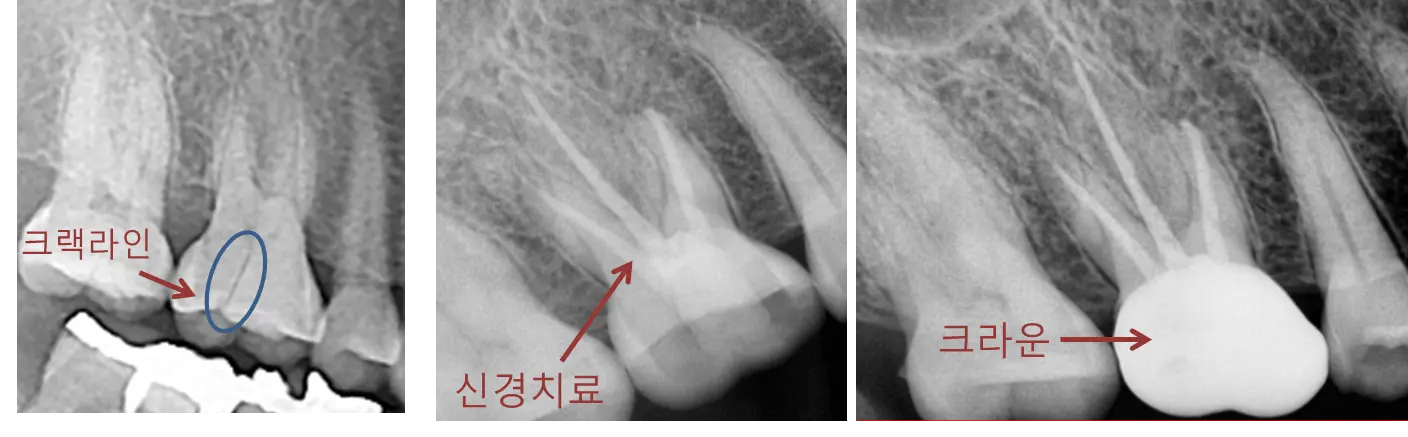

1) 첫번째 관점은 더 이상 금이 진행되지 않도록 하는 것입니다. 한번 금이 간 치아는 그쪽으로 음식물을 씹을 경우 '쐐기효과(wedge effect)'에 의해 더 금이 진행되는 경향이 있습니다. 그래서 치아 절편이 벌어지지 않도록 크라운을 씌워 꽉 붙들어 매주어야 합니다.

2) 두번째 관점은 통증 경감입니다. 신경치료를 통해 신경을 죽이고 통증 감각을 느끼지 않도록 합니다.

크라운 치료를 먼저 할지 아니면 신경치료를 먼저 할지는 현재 환자분이 느끼는 증상에 따라 다릅니다. 당장 가만히 있어도 아프고 그러면 당연히 신경치료를 먼저 빨리 해주어야겠죠.

크랙치아(crack tooth)에 대해서 주로 위와 같이 신경치료+크라운치료를 진행하고, split tooth나 vertical root fracture(VRF)의 경우 치아를 살리는 치료가 거의 어렵다고 보시면 됩니다.